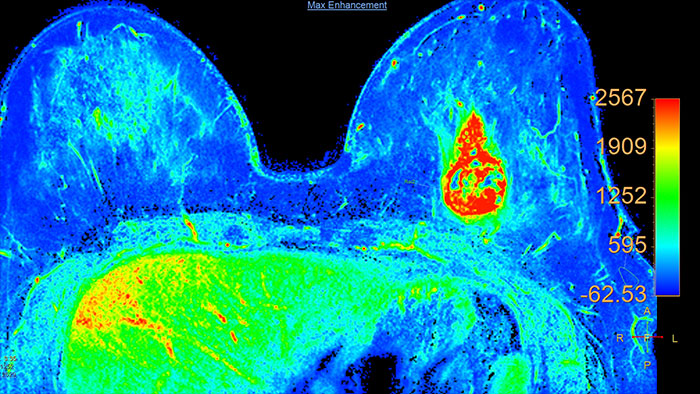

Next generation of breast care

Tailored to enhance the review and analysis of MRI breast studies by providing a flexible workspace with custom hanging protocols and multi-vendor** viewing capabilities. DynaCAD’s automatic segmentation allows on-the-fly user modification and provides volume analysis, lesion composition statistics, histograms, and a 3D rendered morphological overview.

Lesion characterization by reviewing vascular leakage

Designed to visualize T1 weighted DCE 3D datasets and assist in analyzing the tissue response.

Support in assessing lesions by reviewing blood supply characteristics

Designed to evaluate time intensity curves of a T1 signal enhancement series. The application produces measurements including relative enhancement, maximum enhancement, time to peak (TTP), and wash-in/wash-out rates.